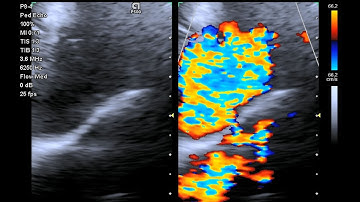

Patent Ductus Arteriosus pda on #echocardiography #heart